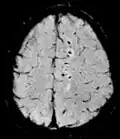

| Effective T2 or "T2-star" |

T2* | Spoiled gradient recalled echo (GRE) with a long echo time and small flip angle[60] | Low signal from hemosiderin deposits (pictured) and hemorrhages.[60] |

| |